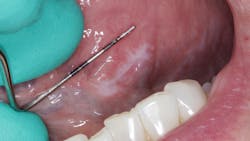

During her routine oral screening and exam, a 9 mm x 3 mm white leukoplakic patch of tissue on the left ventral surface of the tongue was noted. It was not tender to palpation, could not be scraped off, and the patient was unaware of its presence. It was recommended that the patient come back in two to three weeks to assess for continued presence.

The patient was referred to an oral surgeon where evaluation and an excisional biopsy were performed.